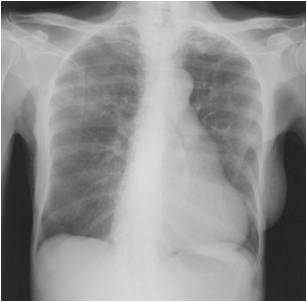

The following are examples of how Active TB may look on CXR:

A CXR reading of “calcified granulomas” is NOT active. Merely the burnt-out remnants of where Mtb first entered the lungs. Simply Latent TB Infection; address the same as a positive PPD / IGRA with “normal CXR”.